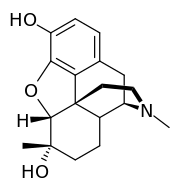

The pharmacodynamic response to an opioid depends upon the receptor to which it binds, its affinity for that receptor, and whether the opioid is an agonist or an antagonist. For example, the supraspinal analgesic properties of the opioid agonist morphine are mediated by activation of the μ1 receptor; respiratory depression and physical dependence by the μ2 receptor; and sedation and spinal analgesia by the κ receptor. Each group of opioid receptors elicits a distinct set of neurological responses, with the receptor subtypes (such as μ1 and μ2 for example) providing even more [measurably] specific responses. Unique to each opioid is its distinct binding affinity to the various classes of opioid receptors (e.g. the μ, κ, and δ opioid receptors are activated at different magnitudes according to the specific receptor binding affinities of the opioid). For example, the opiate alkaloid morphine exhibits high-affinity binding to the μ-opioid receptor, while ketazocine exhibits high affinity to ĸ receptors. It is this combinatorial mechanism that allows for such a wide class of opioids and molecular designs to exist, each with its own unique effect profile. Their individual molecular structure is also responsible for their different duration of action, whereby metabolic breakdown (such as N-dealkylation) is responsible for opioid metabolism.

Several semi-synthetic opioids were developed in Germany in the 1910s. The first, oxymorphone, was synthesized from thebaine, an opioid alkaloid in opium poppies, in 1914.[228] Next, Martin Freund and Edmund Speyer developed oxycodone, also from thebaine, at the University of Frankfurt in 1916.[229] In 1920, hydrocodone was prepared by Carl Mannich and Helene Löwenheim, deriving it from codeine. In 1924, hydromorphone was synthesized by adding hydrogen to morphine. Etorphine was synthesized in 1960, from the oripavine in opium poppy straw. Buprenorphine was discovered in 1972.[228]